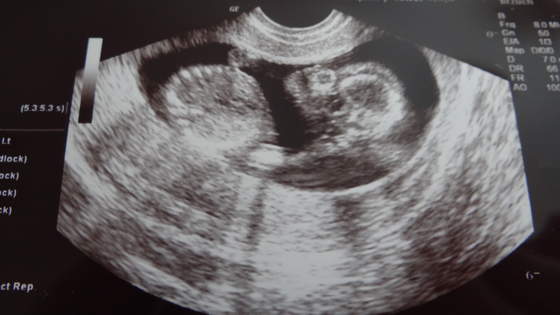

No i zerkamy na płeć (of kors nic nie mówiłam, że tydzień temu byłam gdzie indziej i lekarka sugerowała, że to mógłby być chłopiec). A gin mówi, że na 95% dziewczynka

No i rzeczywiście, już żadnego cypelka nie widać!!! A podobieństwo tego obrazu do tego jak dowiedzieliśmy się w I ciąży, że będzie dziewczynka uderzające!!! Wow, ale byłoby super! Szczególnie, że marzyliśmy o drugiej dziewczynce.